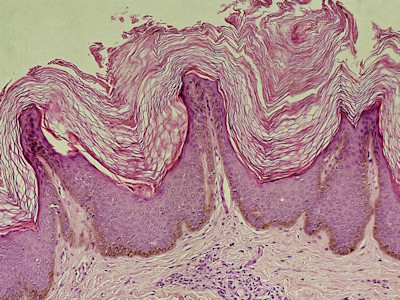

PA:Hyperkeratotische epidermis met hoogoplopende

papillen met vingervormïge projecties; onregelmatige

acanthose en hyperkeratose. Sterk aan elkaar hechtende, opeengepakte

pigmenthoudende corneocyten. Relatief normaal aantal melanocyten, maar sterk

verlengde retelijsten, hetgeen door overprojectie bijdraagt tot de

hyperpigmentatie. De oppervlakkige dermis toont een minimaal perivasculair infiltraat.

PAS-kleuring: geen pityrosporum.

| PA

acanthosis nigricans |

PA